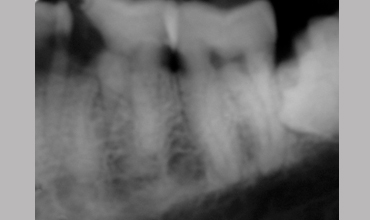

Management Of Radix

Management Of Radix Entomolaris In Mandibular First Molar